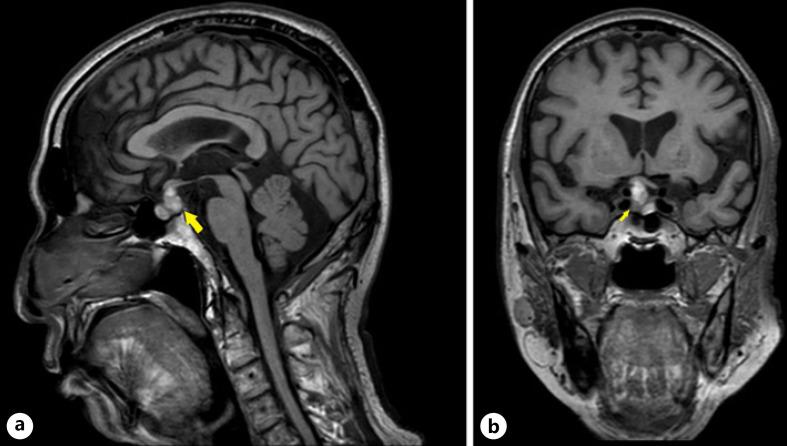

Pituitary adenoma can manifest as pituitary hypofunction, which can cause symptoms of panhypopituitarism. Commonly, symptoms of hormonal deficiencies such as lethargy, weight change, cold intolerance, and sexual dysfunction are reported. Optic chiasmal compression leads to visual field changes and the discovery of the pituitary lesion. However, limb stiffness is a rare presentation of hypopituitarism, especially hypocortisolism. We report a 68-year-old man who presented with progressive lower limb stiffness associated with truncal instability mimicking a stiff person syndrome (SPS). Hypoglycaemia and hyponatraemia prompted the discovery of pituitary macroadenoma with panhypopituitarism. Investigation showed pituitary macroadenoma on magnetic resonance imaging with hypocortisolism, hypothyroidism, and hypogonadotropic hypogonadism. After initiating hydrocortisone replacement, the patient had complete resolution of lower limb stiffness with no permanent neurological sequelae. It is postulated that hypocortisolism and hyponatraemia disrupt the metabolic function of muscle leading to stiffness. As a result, lower limb rigidity, flexion deformities, and pain are more common. Differentiating adrenal insufficiency associated with rigidity and SPS is important as the response to treatment for both conditions differs. Prompt treatment leads to fast resolution and prevents contractures in adrenal insufficiency-associated rigidity. Thus, recognizing limb rigidity as the first presentation of hypopituitarism is important to avoid long-term complications.

垂体腺瘤可表现为垂体功能减退,进而导致全垂体功能减退的症状。常见的是出现如嗜睡、体重变化、不耐寒及性功能障碍等激素缺乏症状。视交叉受压会导致视野改变以及垂体病变的发现。然而,肢体僵硬是垂体功能减退尤其是皮质醇缺乏症的一种罕见表现。我们报告一例68岁男性,表现为进行性下肢僵硬并伴有躯干不稳,类似僵人综合征(SPS)。低血糖和低钠血症促使发现垂体大腺瘤伴全垂体功能减退。检查显示磁共振成像发现垂体大腺瘤,伴有皮质醇缺乏、甲状腺功能减退和低促性腺激素性性腺功能减退。开始氢化可的松替代治疗后,患者下肢僵硬完全缓解,无永久性神经后遗症。据推测,皮质醇缺乏和低钠血症会破坏肌肉的代谢功能,导致僵硬。因此,下肢僵硬、屈曲畸形和疼痛更为常见。区分与僵硬相关的肾上腺功能不全和SPS很重要,因为这两种情况的治疗反应不同。及时治疗可快速缓解并预防肾上腺功能不全相关僵硬中的挛缩。因此,将肢体僵硬识别为垂体功能减退的首发表现对于避免长期并发症很重要。